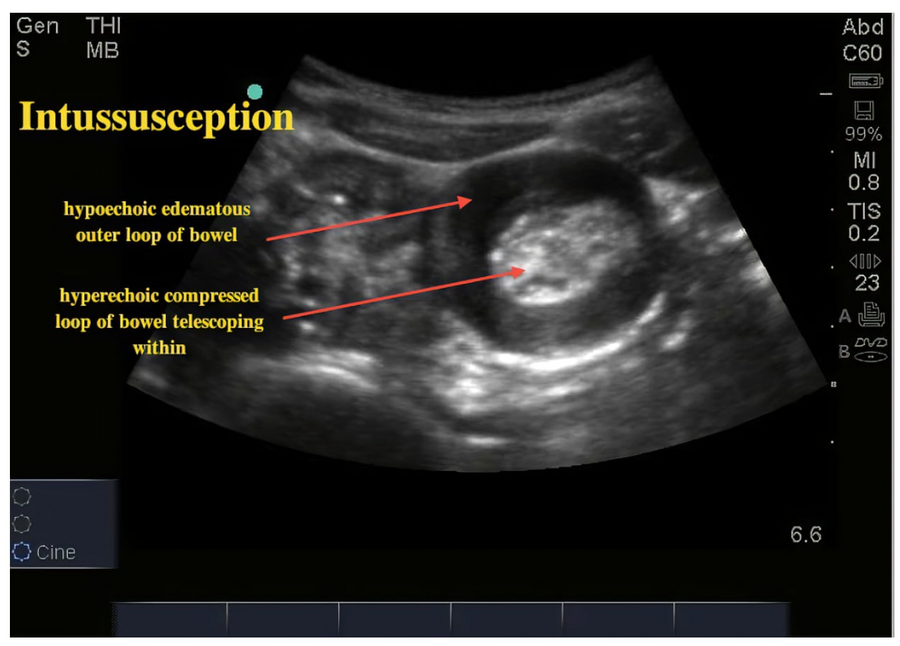

- Ultrasound is primary test for diagnosis (negative predictive value is ~100%)

- Classic "target sign" appearance, usually located in the right lower quadrant (ileo-cecal region)

Source: Ultrasound Cases

Q3. Diagnosis is made by ultrasound, which typically shows the “target sign” in the right lower quadrant. A two-view abdominal radiograph is often obtained beforehand to rule out perforation.

Q8. Intussusception. The “target sign” on ultrasound confirms the diagnosis.